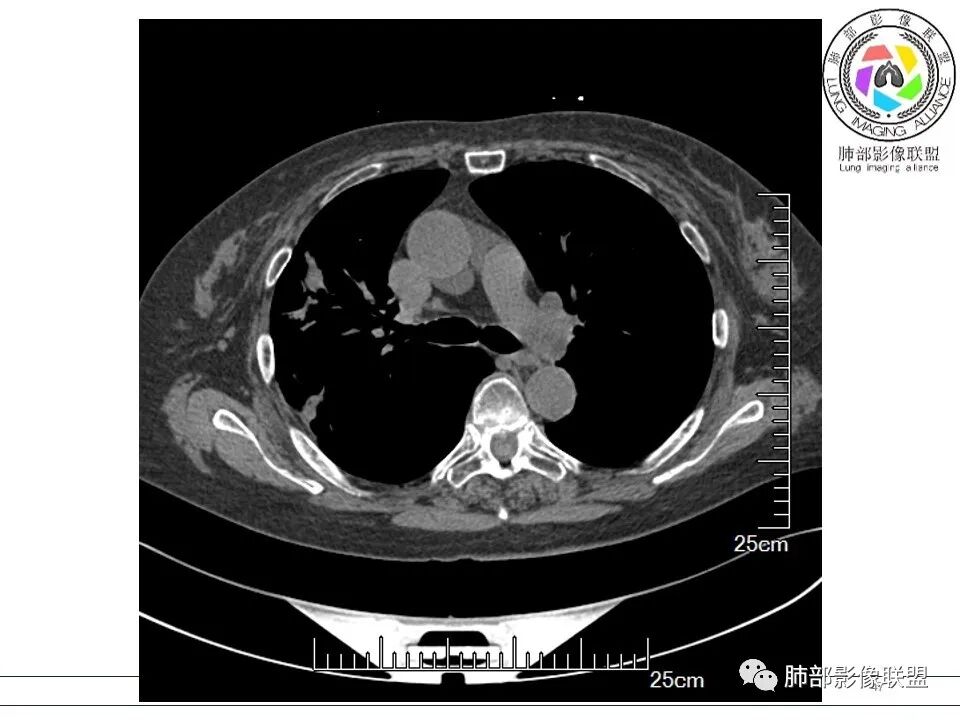

晨读:女,70,未诉症状。风湿性多肌痛病史,口服强的松等药物治疗。胸部CT:右肺上叶多发不规则斑片影,沿支气管分布,部分病灶侧向融合、平行于胸膜,边缘平直内收为主、部分彭隆,周围模糊晕、可见数条纤维灶影,胸膜牵拉,病灶内可见充气支气管征、管腔不畅,考虑慢性炎症,PC?OP?鉴别腺Ca、SCLC等。

南边: 这个病例大方向没问题,炎性。目前大家都是考虑:隐球菌病、OP,其实这两个结论有重叠,而且这个病例很值得讨论,可惜,估计没有证实。影像特点:病灶长轴与胸膜平行,侧向融合特点明显,符合隐球菌病,问题是目前的状态,边缘收缩明显

内部支气管扩张,周围少量GGO,而且病灶离开了胸膜,附近长索条影,支持机化的改变

5、分布:隐球菌肺炎是肺泡性炎症,病灶分布多位于胸膜下,可紧贴胸膜,也可与胸膜邻近,病灶长轴与胸膜平行。(划重点,分布特点非常重要,因为隐球菌如果没有荚膜,会被巨噬细胞吞噬,在人体内是无法生存。隐球菌孢子吸入后,要有高浓度的CO2的条件下,才能形成荚膜,所以肺泡内、胸膜下多见)

6、支气管和血管:支气管通畅或进入后堵塞,增强可见血管造影征或血管影消失。

7、强化:增强强化程度各异,从轻度到中度强化均可。明显/显著强化相对少见。